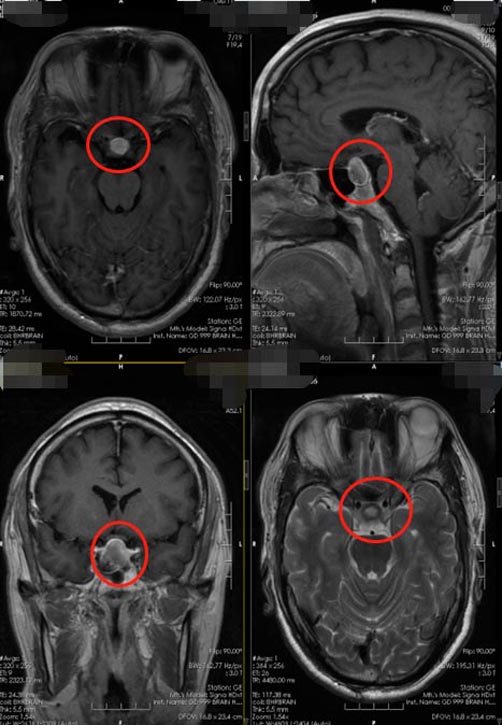

家人再三考虑后,来到了广东三九脑科医院神经外五科。头颅MR检查提示“鞍区异常信号,待排垂体Rathke’s囊肿或垂体瘤卒中”。患者具有手术指征,和家属沟通病情后,由医院副院长、神经外五科主任鲁明主刀“行内镜经鼻蝶鞍区占位切除术”,在中鼻甲与鼻中隔之间收缩粘膜,制作鼻中隔粘膜瓣,磨除蝶窦前壁,进入蝶窦,刮除窦内粘膜,磨除鞍底骨质,钩刀“+字型”全层切开硬脑膜,见灰色、豆腐渣样结晶,质地一般,剪开鞍结节硬膜,进一步探查垂体柄,将病变全切;无脑脊液漏,探查未见病变残留。

▲术前